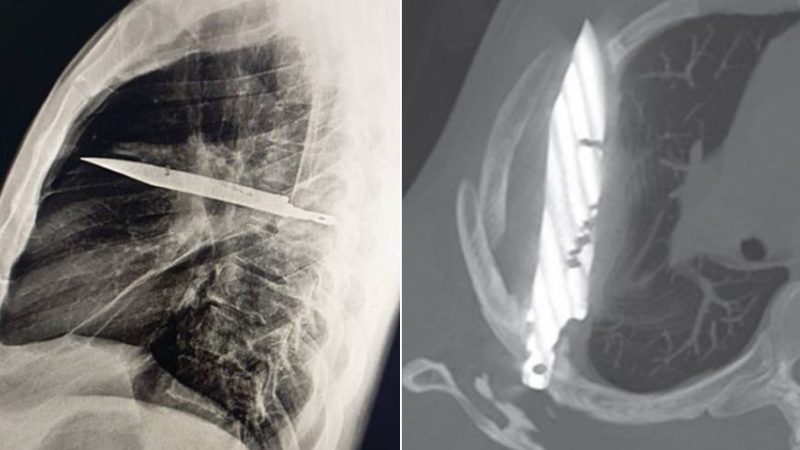

A chest X-ray revealed the shocking truth: a knife was embedded in his chest cavity, having entered near his right shoulder blade while miraculously avoiding all vital organs.